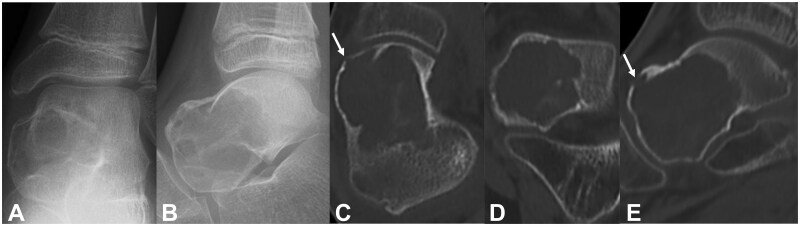

Aneurysmal bone cyst (ABC) is a locally destructive benign tumour-like condition of the bones with blood-filled cystic cavities. The talus is an extremely rare site for an ABC, with <20 reported cases till 2012 based on a PubMed database search. Aneurysmal bone cyst recurrence in the talus after curettage and bone grafting is extremely rare. To the best of our knowledge, no detailed reports of resection and adjuvant therapy with artificial bone packing of recurrent ABC of the talus have been published. We report a case of ABC in the talus of a 9-year-old boy. As the initial surgery consisted of only lesion resection and artificial bone (beta-tricalcium phosphate [TCP]) packing, local recurrence was diagnosed. Reoperation was performed 5 months after the initial surgery. The recurrent lesion was resected using a curette, and the bone cavity septum was shaved with a high-speed burr. Phenol-ethanol ablation was used as an adjuvant with artificial bone (beta-TCP) packing to prevent recurrence. No local recurrence was observed 36 months after the reoperation. This extremely rare case of resection and adjuvant therapy with artificial bone packing of recurrent ABC of the talus highlights the need for careful observation to assess the progression of ankle joint osteoarthrosis.

Abstract Image